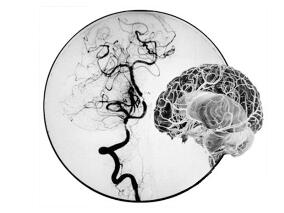

急性缺血性卒中的干预

1小时条评论2016年6月,发表于《J Am Coll Cardiol》的一项综述性研究探讨了近年来急性缺血性卒中干预治疗的发展。 急性缺血性卒中(AIS)是全世界主要的致残原因,也是一个主要的死亡原因。尽管20年前就批准静脉内组织型纤溶酶原激活物(IV-rtPA)治疗AIS,但由于治疗的窄时间...